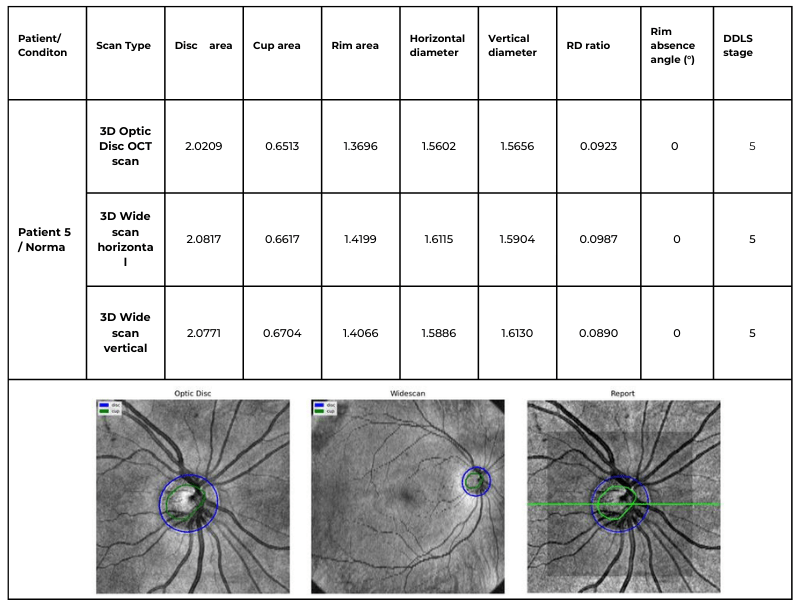

Dr. Maria Sampalis, OD, the owner of Sampalis Eye Care, Rhode Island, utilizes two such programs in her practice. To support her specialization in dry eye management, she employs CSI Dry Eye. Additionally, she uses Altris AI, an AI-powered platform for OCT scan analysis, to provide a second opinion and enhance diagnostic accuracy.

Dr. Sampalis finds that the Dry Eye software allows her and her staff to analyze symptoms and images comprehensively, improving patient care, time savings, and increasing diagnostic precision. See how OCT AI works here.

Her patients also appreciate Altris AI, which analyzes OCT scans for over 70 pathologies and biomarkers while also calculating the risk of developing glaucoma.

Eye Place, an optometry center in Columbia, also leverages Altris AI, among other cutting-edge technologies. They capture images using the Topcon Maestro2 OCT and use Image Net6 software to export DICOM files to the Altris AI platform.

Beyond AI-powered OCT analysis, Eye Place utilizes state-of-the-art diagnostic tools, such as 3D OCT equipment, to screen for serious conditions, including glaucoma, diabetes, and macular degeneration. Furthermore, they work with AdaptDX Pro, a technology capable of detecting macular degeneration earlier than traditional methods.